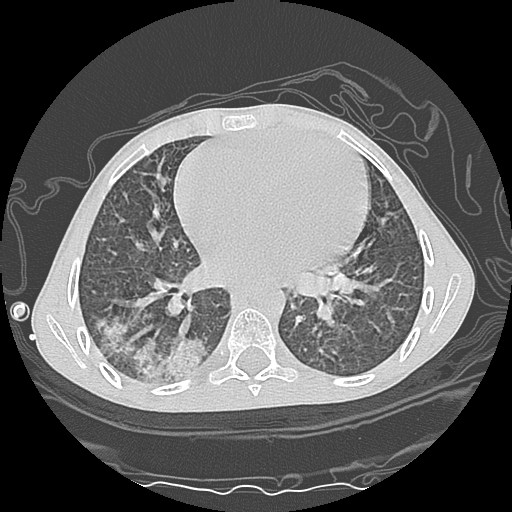

- Computerized tomography (CT) of chest.

| CT3 | CT4 | CT5 |